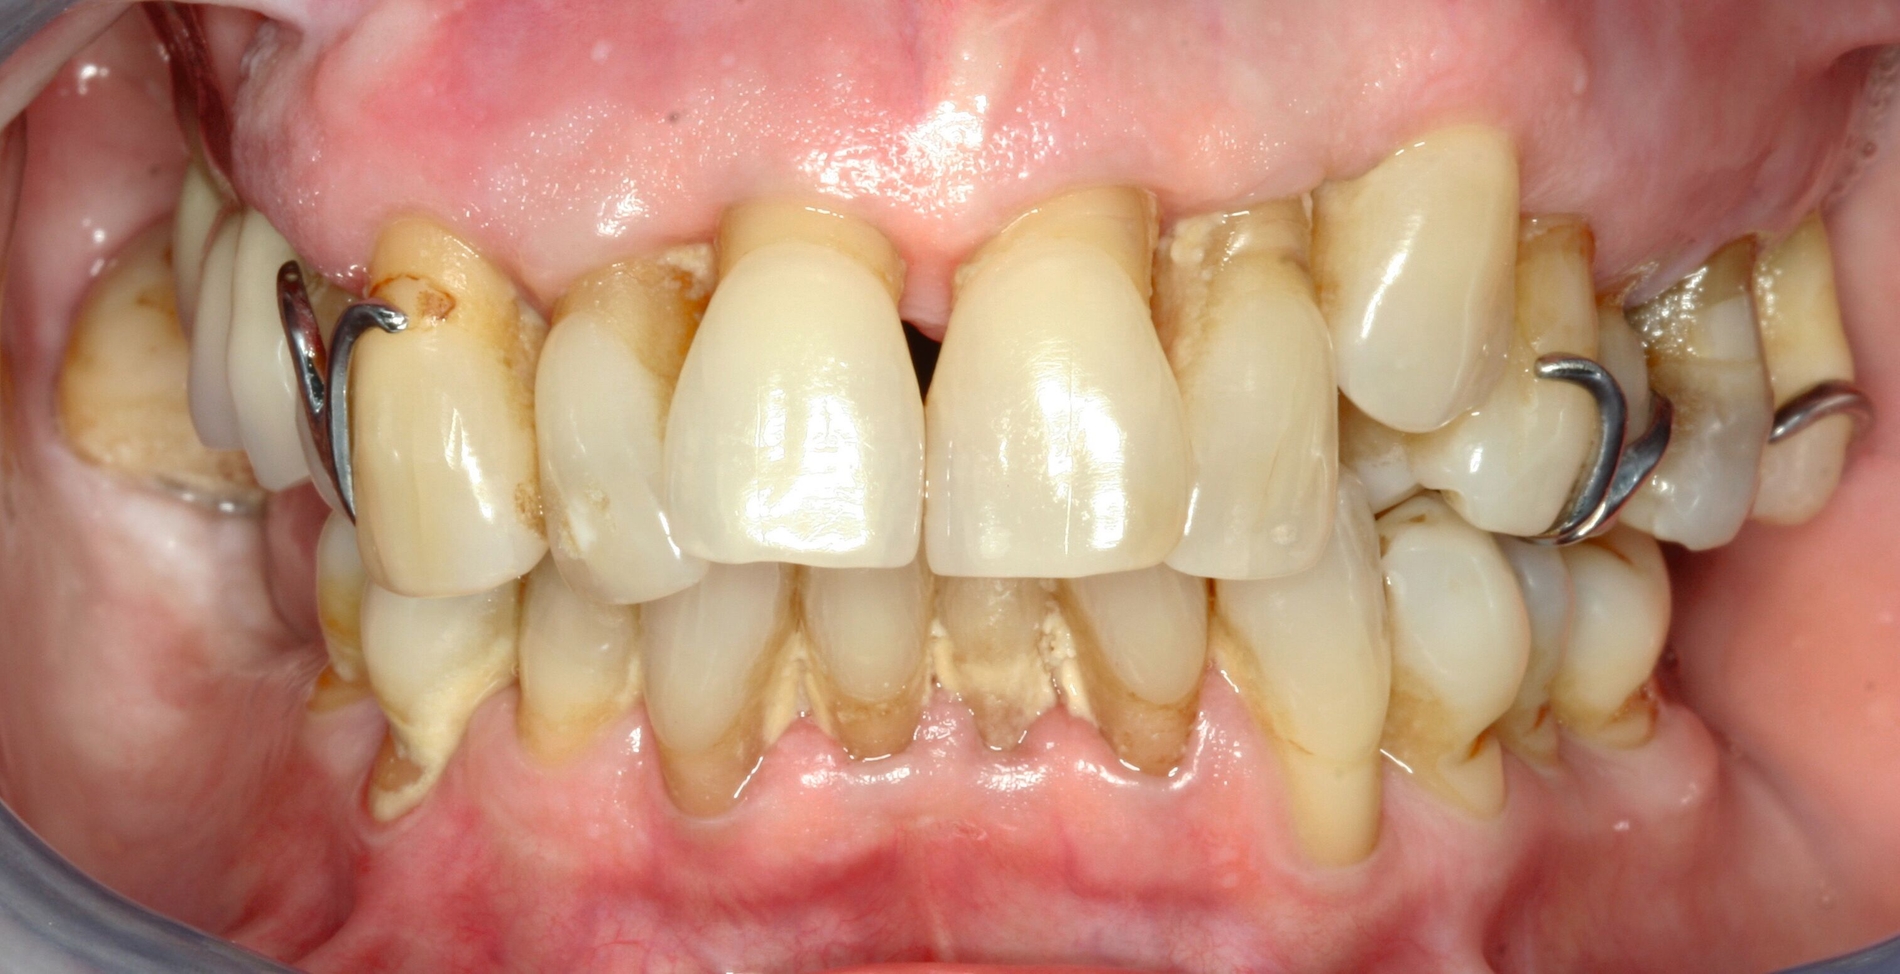

Eine 74-jährige Patientin erhielt eine Modellgussprothese im Oberkiefer zur Abdeckung einer Mund-Antrum-Verbindung infolge der Resektion eines malignen Befunds im Bereich des Alveolarfortsatzes rechtsseitig (Abbildung 1). Trotz mehrfacher Umarbeitungen gelang eine Adaption an den Zahnersatz nicht. Die Patientin empfand die Klammern als zu scharf und spitz. Zudem störte sie sich an der Ästhetik. Die Mundhygiene war gut, nur wenige Zähne besaßen eine Füllung. Es bestand eine hohe Erwartungshaltung an den Zahnersatz.

Bezogen auf die Belastbarkeit lagen zum damaligen Zeitpunkt trotz der Malignomtherapie keine Einschränkungen vor (BS 1). Dem Wunsch der Patientin nach einem Klammer-freien Zahnersatz konnte mit regulärem Therapieaufwand entsprochen werden (Abbildung 2). Nach dessen Eingliederung gelang eine rasche Gewöhnung. Die Patientin erschien viele Jahre regelmäßig zur professionellen Zahnreinigung und zur Kontrolle. Zahnmedizinische Interventionen waren nicht erforderlich.